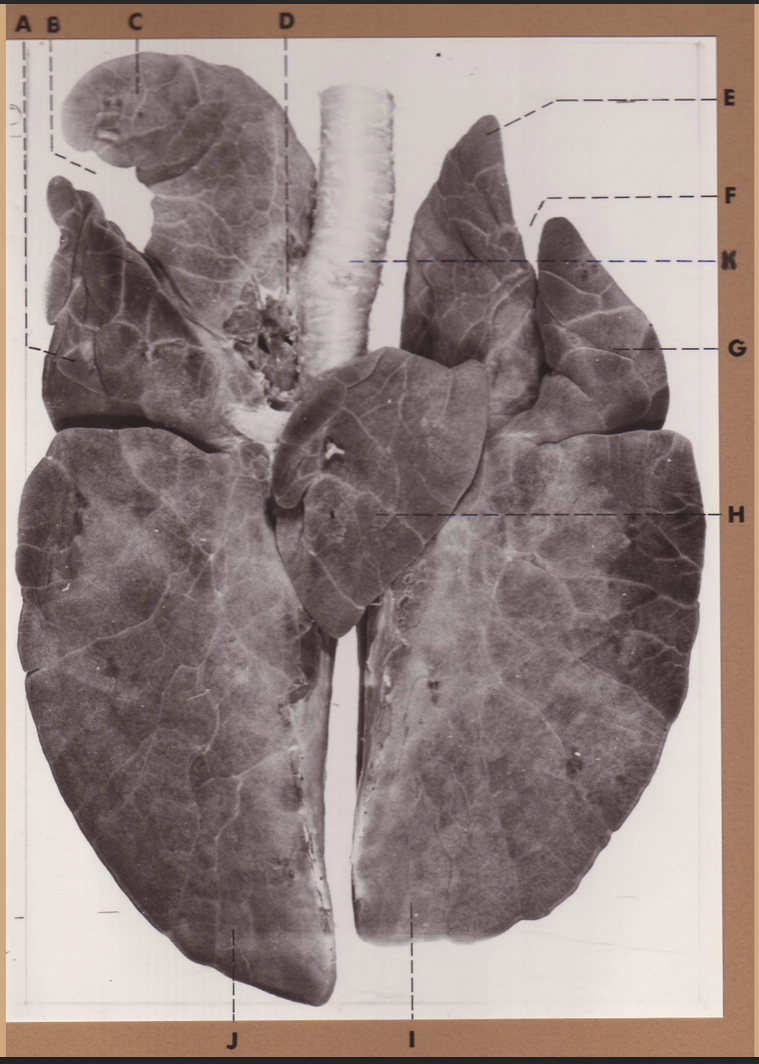

A

(cat larynx/trachea/lungs, dorsal)

epiglottis

B

(cat larynx/trachea/lungs, dorsal)

larynx

C

(cat larynx/trachea/lungs, dorsal)

trachea

D

(cat larynx/trachea/lungs, dorsal)

R cranial lobe

E

(cat larynx/trachea/lungs, dorsal)

middle lobe

F

(cat larynx/trachea/lungs, dorsal)

R caudal lobe

G

(cat larynx/trachea/lungs, dorsal)

primary bronchi

H

(cat larynx/trachea/lungs, dorsal)

L caudal lobe

I

(cat larynx/trachea/lungs, dorsal)

L cranial lobe

J

(cat larynx/trachea/lungs, dorsal)

cricoarytenoideus dorsalis m

K

(cat larynx/trachea/lungs, dorsal)

thyroid

A

(cat larynx/trachea/lungs, dorsal)

epiglottis

B

(cat larynx/trachea/lungs, dorsal)

larynx

C

(cat larynx/trachea/lungs, dorsal)

trachea

D

(cat larynx/trachea/lungs, dorsal)

R cranial lobe

E

(cat larynx/trachea/lungs, dorsal)

middle lobe

F

(cat larynx/trachea/lungs, dorsal)

R caudal lobe

G

(cat larynx/trachea/lungs, dorsal)

primary bronchi

H

(cat larynx/trachea/lungs, dorsal)

L caudal lobe

I

(cat larynx/trachea/lungs, dorsal)

L cranial lobe

J

(cat larynx/trachea/lungs, dorsal)

cricoarytenoideus dorsalis m

K

(cat larynx/trachea/lungs, dorsal)

thyroid